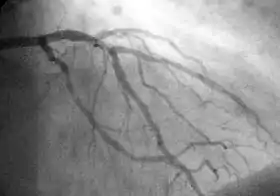

Coronary catheterization

Coronary catheterization uses pressure monitoring and blood sampling through a catheter inserted into the heart through blood vessels in the leg or wrist to determine the functioning of the heart, and, following injections of radiocontrast dye, uses X-ray fluoroscopy, typically at 30 frames per second, to visualize the position and volume of blood within the heart chambers and arteries. Coronary angiography is used to determine the patency and configuration of the coronary artery lumens.